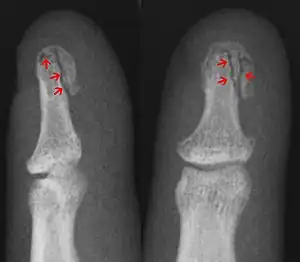

| A mallet finger due to an avulsion fracture | |

Fractures in the joints are often caused by jammed finger injuries, the hand equivalent of a stubbed toe. If a tendon pulls away the bit of bone to which it is attached (an avulsion fracture, shown in the image at the top of the page), that will also lead to a fracture in a joint.[3]